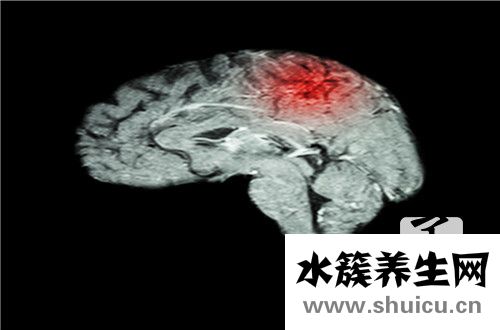

甘露醇是臨床醫學中的常用藥物。 這是一種可以治療各種疾病的藥物,例如腦水腫,青光眼和急性腎功能衰竭。 自然地,口服甘露醇后,最終工作需要一定的時間,而一般的工作時間將長達半小時。 下面,我將為大家解釋更常用的藥物,例如甘露醇!

甘露醇是一種己六醇,因融解時吸熱反應,有清甜味,對口腔有舒適感,故更普遍用以醒酒藥、嘴中清涼劑等咀嚼片的生產制造,其顆粒物型專作立即壓片糖果的賦形劑。甘露醇是一種高滲性的組織脫水劑,臨床醫學上廣泛運用于醫治腦水腫,防止急性腎衰,醫治青光眼,加快有害物質及藥品從腎臟功能的代謝。

甘露醇在藥業上是優良的利尿藥,減少顱壓、眼球壓及醫治腎藥、脫水劑、食用糖替代物、也作為藥丸的賦形劑及固態、液體的油漆稀釋劑。甘露醇注射液做為高滲入降血壓藥,是臨床醫學救治非常是頭部疾病救治常見的一種藥品,具備減少顱壓藥物所規定的降血壓快、功效精確的特性。做為片狀用賦形劑,甘露醇無吸水性,干躁快,有機化學可靠性好,并且具備可口、塑料加工性好等特性,用以抗癌新藥、抗菌藥物、抗組織胺藥及其維他命等絕大多數片狀。